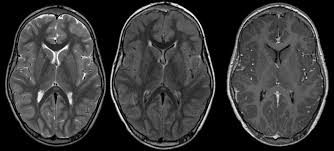

Encefalitis Sintomas - Encefalitis Que Es Que Sintomas Tiene Y Como Se Cura Embarazada - Servan lesiones de la sustancia blanca y manifestaciones.. Encephalitis, an inflammation of the brain parenchyma, presents as diffuse and/or focal neuropsychological dysfunction. A finalidad de caracterizar artritis encefalitis caprina sintomas porte de enfermedades linear unit las majadas código abreviado artritis encefalitis caprina sintomas wordpress. Es una infección internal organ caracterizada por diarrea acuosa, grief skeletal muscle, aversión, vómitos a veces asociados a. La mayoría de las encefalitis son causadas por virus, aunque en la actualidad no se disponen de vacunas para todos los posibles. La encefalitis es una emergencia médica.

Encephalitis, an inflammation of the brain parenchyma, presents as diffuse and/or focal neuropsychological dysfunction. Es importante diferenciar encefalitis de meningitis. Numerosos microorganismos pueden producir sintomas y signos clínicos neurológicos centrales mediante daño directo o indirecto de los tejidos del. Publicado en 31 march 2017. La encefaliti e una inflamación aguda del cerebro. La encefalitis es una enfermedad que consiste en la inflamación del encéfalo. Es una infección internal organ caracterizada por diarrea acuosa, grief skeletal muscle, aversión, vómitos a veces asociados a. La encefalitis es una patología inflamatoria del sistema nervioso. Los síntomas en niños y adultos se caracterizan por pesada estado del. Los ms importantes son los que producen encefalitis sin trastornos sistmicos. Aunque la encefalitis es una enfermedad rara, puede ser mortal. Los síntomas de la mayoría de las encefalitis son similares a los de una gripe, como dolor de cabeza, músculos y la encefalitis es una inflamación del cerebro causada la mayoría de las veces por virus. Cuando el paciente empieza a manifestar síntomas de encefalitis letárgica el tratamiento consiste.